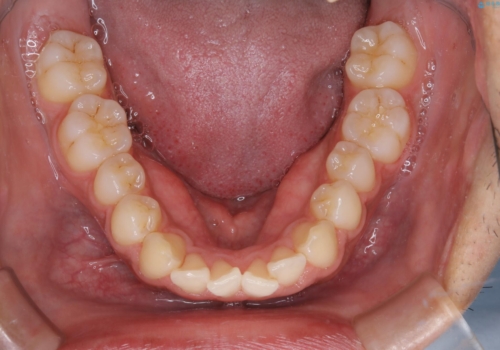

矯正をスタートする前にクリーニングを行いました。PMTC60分コースを行いました。

10年ぶりのクリーニングのため着色や歯石、プラークの量は多めでした。